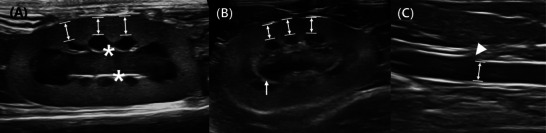

在这项回顾性多中心研究中,我们旨在建立肾皮质厚度-主动脉直径(RCT:Ao)比值作为诊断猫急性肾损伤或慢性肾脏疾病(AKI或CKD)的诊断参数。本研究包括152只正常猫、171只CKD猫、19只AKI猫和15只急性/慢性肾病猫的双侧肾脏。在肾脏和主动脉正中矢状面进行超声测量。RCT与体重(BW)、体况评分(BCS)的多元线性回归分析显示,RCT与体重(BW)呈正相关(p

In this retrospective multicenter study, we aimed to establish the renal cortical thickness-aortic diameter (RCT:Ao) ratio as a diagnostic parameter for detecting feline acute kidney injury or chronic kidney disease (AKI or CKD). This study included bilateral kidneys of 152 normal, 171 CKD, 19 AKI, and 15 acute-on-chronic kidney disease (ACKD) cats. Ultrasonographic measurements were obtained in the midsagittal plane of the kidneys and aorta. Multiple linear regression analysis of RCT, body weight (BW), and body condition score (BCS) revealed a positive correlation of RCT with BW (p < 0.001), but not with BCS (p = 0.343). Multiple linear regression analysis of RCT:Ao ratio, BW, and BCS showed a poor model fit (F value: 0.119). There were significant intergroup differences among the normal, CKD, AKI, and ACKD sub-cohorts (p < 0.001). Compared to normal cats, CKD and AKI cats each had lower and higher RCT:Ao ratio (both p < 0.001), respectively. The RCT:Ao ratio of the ACKD group significantly differed from that in normal and CKD groups (both p < 0.001), but not the AKI group (p = 0.159). Optimal RCT:Ao ratio cutoffs of 1.15 and 1.45 were used to distinguish between the normal and CKD groups (75% sensitivity, 80% specificity) and the normal and AKI groups (90% sensitivity, 89% specificity), respectively. The RCT:Ao ratio was unaffected by the BW and BCS and is a clinically useful diagnostic parameter for feline kidney disease.